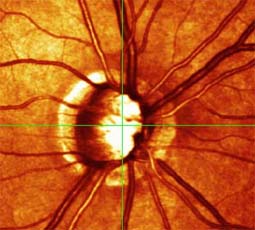

Očekávali byste protažení exkavace k hornímu pólu terče, jak nám ukazuje tento snímek z tomografu HRT II.

exkavace levé oko